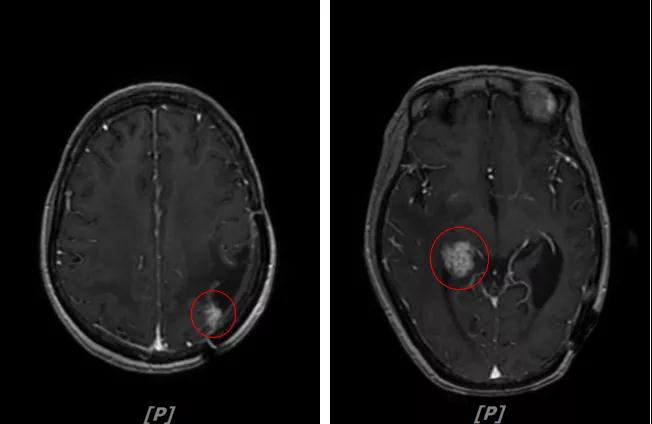

3.病情第2次进展: 2016年12月患者再次出现头痛症状

头颅增强MR:左侧顶枕叶见片状T1WI低信号、T2WI高信号影,增强后病灶边缘见局部斑片状强化改变,邻近脑膜轻度强化改变;右侧脑室三角区内侧见大小约8x14mm的结节影,T1WI低信号、T2WI等高信号,增强明显强化,灶周水肿明显;两侧脑室旁见片状异常信号,T1WI低信号,T2WI高信号,增强未见明显强化,余脑室、脑池、脑沟大小形态可,中线结构居中无移位

左顶叶脑转移瘤术后放疗后,左顶叶术区边缘强化灶;考虑肿瘤复发

右侧脑室三角区内侧转移瘤

两侧脑室旁云絮状异常信号,考虑放疗后改变

患者一线治疗的PFS为37个月。2017年1月,患者二线治疗为在原“拉帕替尼+阿那曲唑”基础上,加曲妥珠单抗治疗。患者头痛症状有所改善,病灶缩小,继续定期复查。